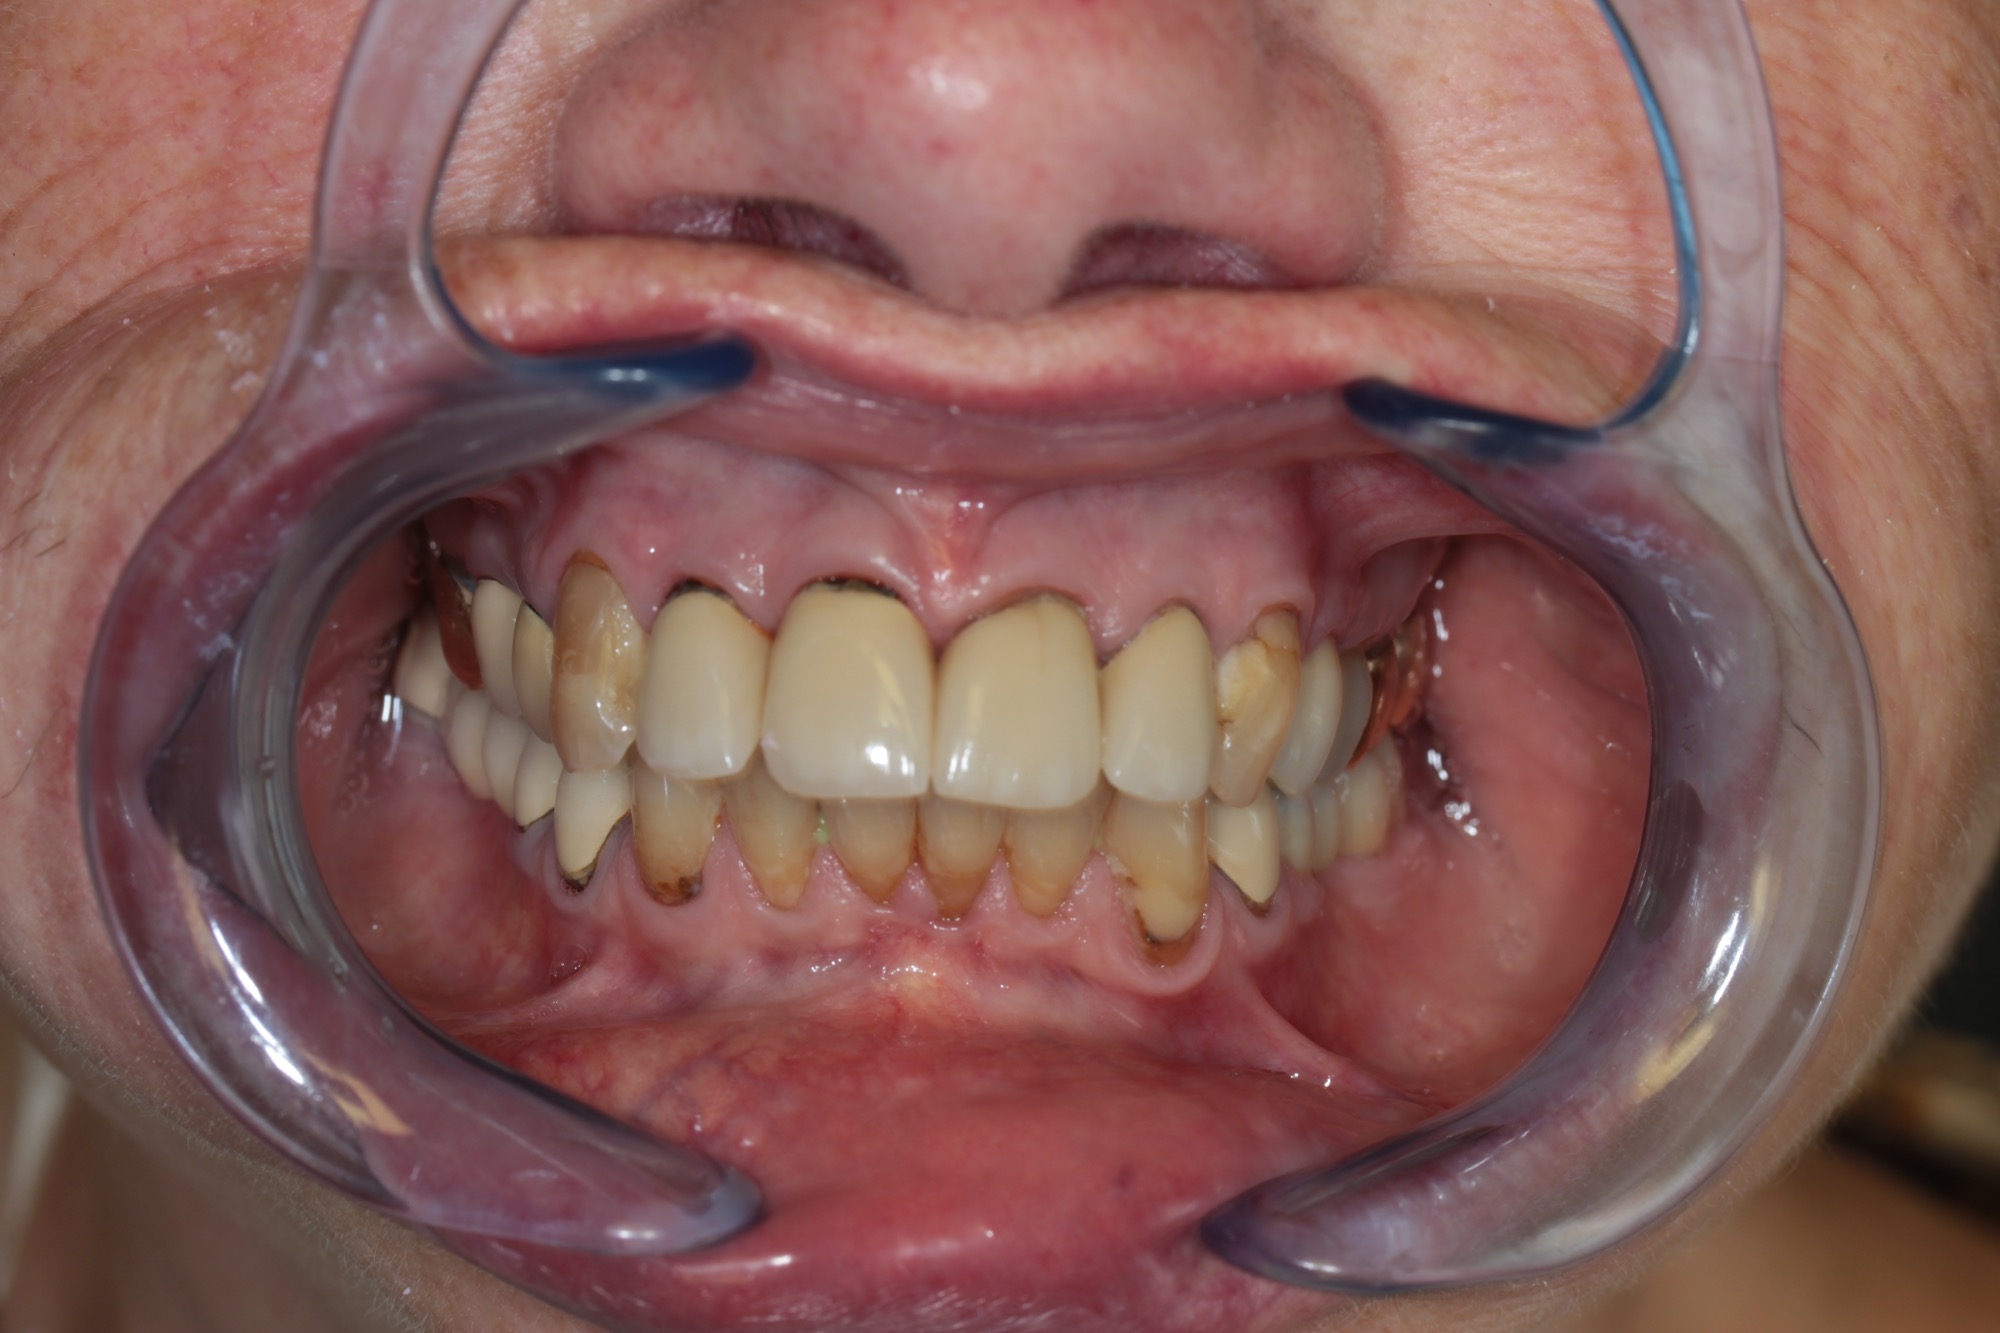

Teleskopierende Oberkieferbrücke mit Vorher- und Nachher-Situation des Patienten.

Teleskopierende Oberkieferbrücke. Wie die eigenen Zähne, aber einfach zu reinigen.